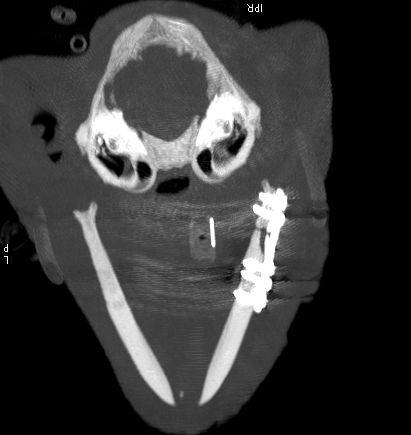

Both post op CT scans – Axial image from a post-operative CT scan showing excellent reduction of the fracture